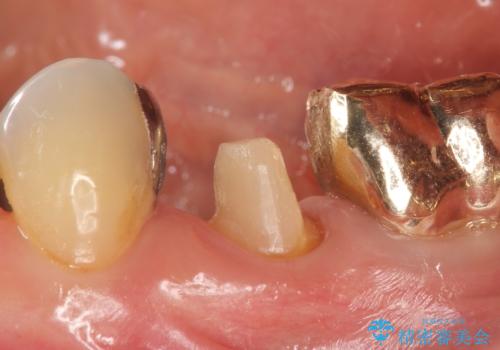

- 左下5番目の歯を根管治療からやり直したいといらっしゃった方の症例です。

再根管治療終了後、オールセラミッククラウンによる補綴を行いました。